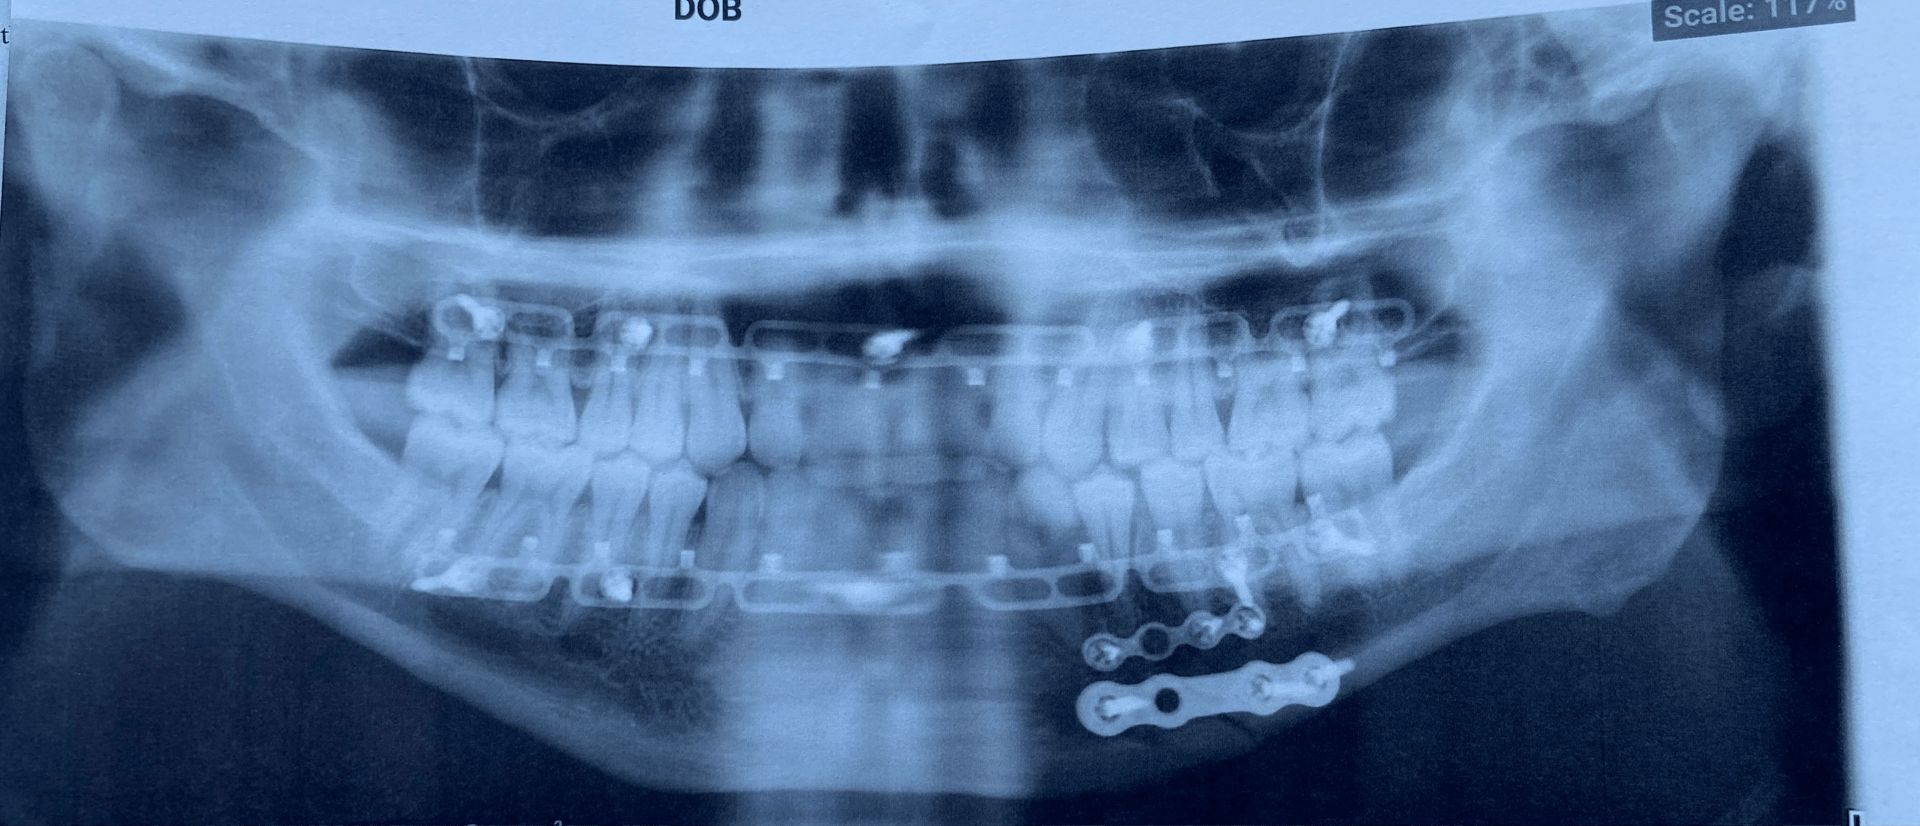

My entire journey started February, 2022. 24 years old, watching pro wrestling, playing video games, little to no physical activity, and yet still my mind wandered to “I want to be a pro wrestler”. I thought to myself ‘could I do it, would I even be able to keep up’, well, a few live WWA4 shows later and I was in a ring training to live out my dreams. It didn’t take long for me to find out how painful this journey would be. A year later I broke my jaw during a match but I did not stay down. I kept fighting, not just during the match, but after especially. With my hand raised in victory, I spoke to the crowd with my jaw hanging off my face to further prove my passion prevails. However, I was in for a rude awakening; 16 screws, 2 brackets and 2 plates later, I was on the shelf for multiple months as I recovered from my broken jaw. The support I had during and after my recovery was astounding and if it weren’t for my Princess of Passion, I likely wouldn’t be the pro wrestler you see before you. Setbacks happen more often than not and it’s up to us to figure a way to fight through it. I like to think of it like a slingshot, all the bad will pull you back further and further making you believe there’s no way out, until you let go and fling into the good that was waiting for you all along. I want everyone to know to never give up, your passion whatever it may be will prevail and you will succeed the more you allow yourself to let go and fling into success.